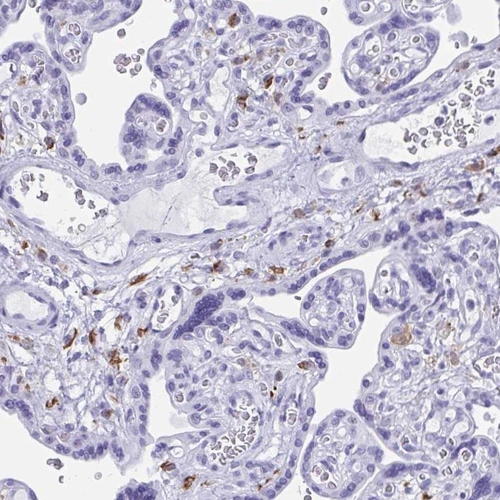

Immunohistochemical staining of human placenta shows distinct positivity in subsets of cells.